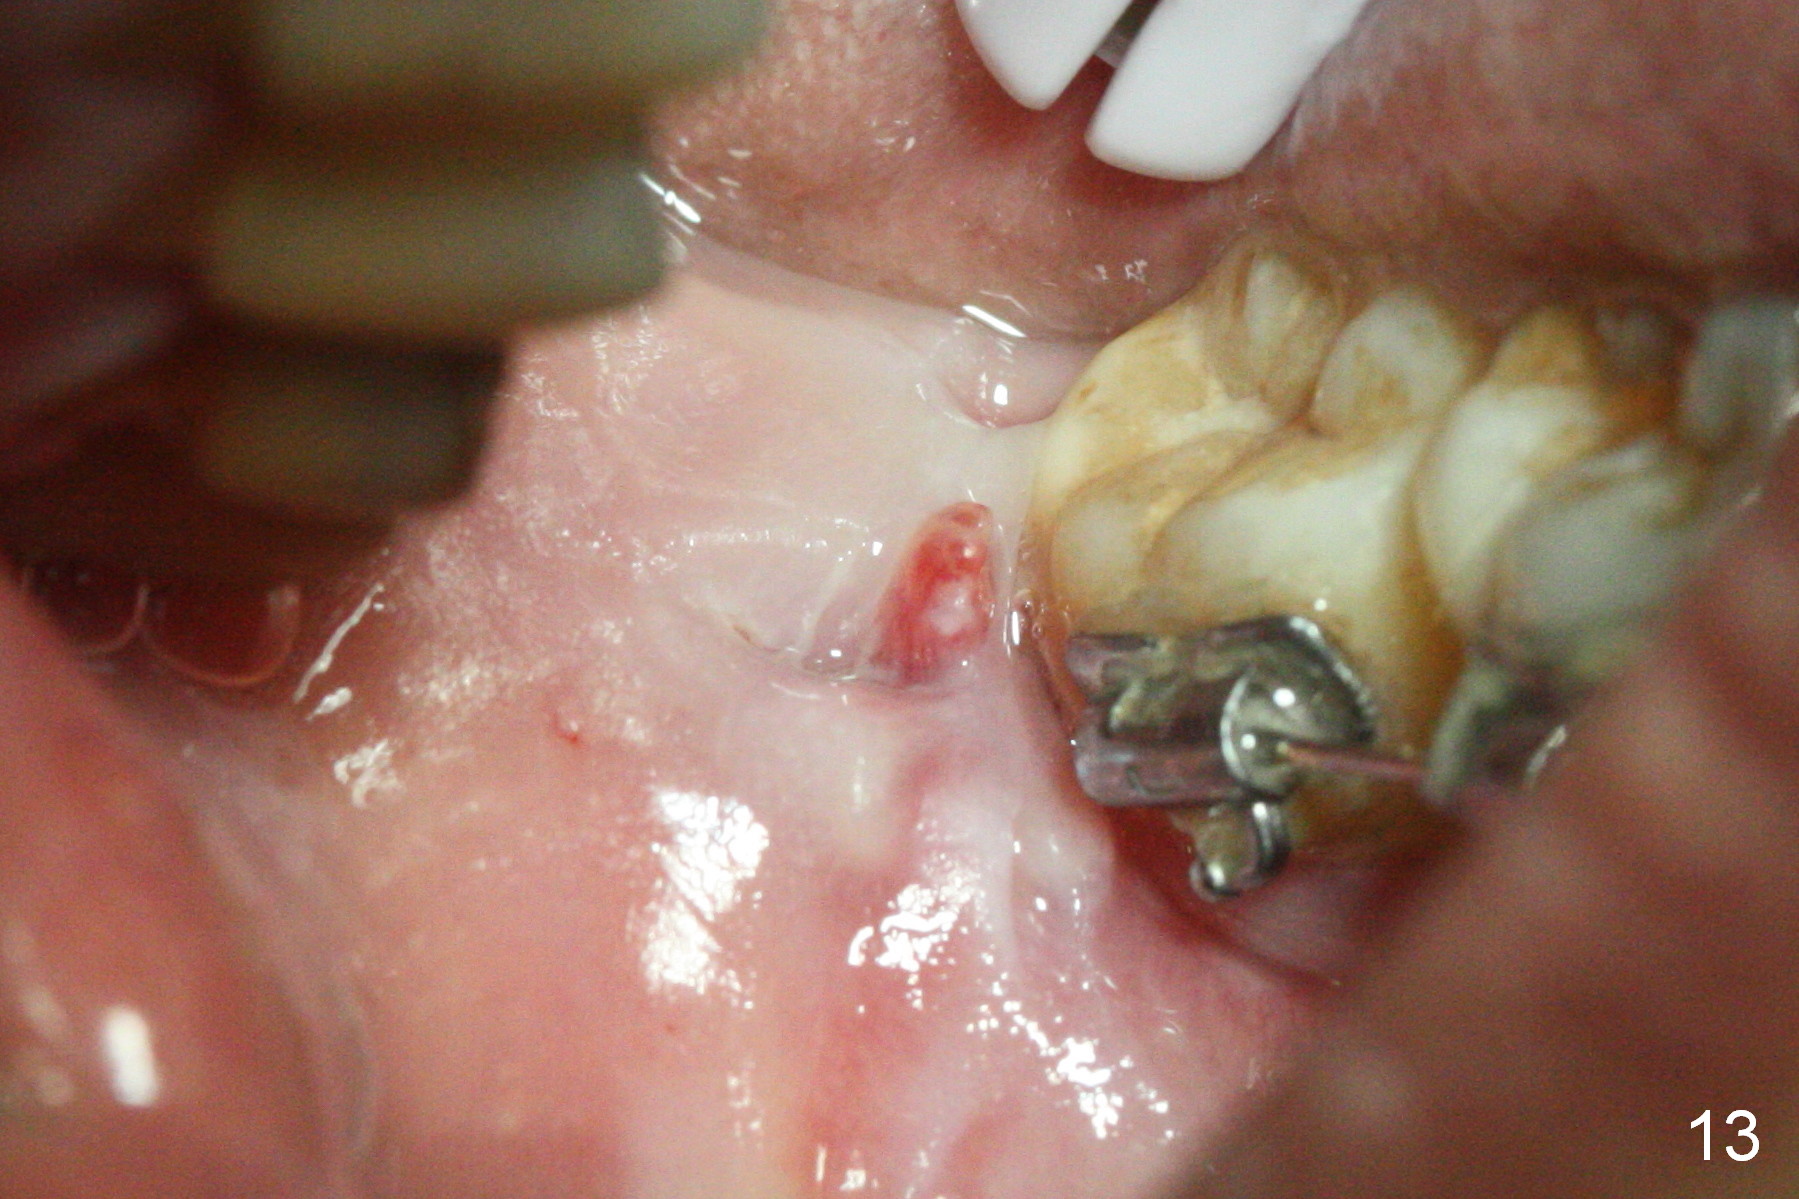

Once the ligature wire connecting the mini implant and closed coil spring fractures inside the wound, it is difficult to replace, causing localized inflammation (Fig.13, 8 months post placement). The wire and the mini-implant need a 2nd difficult surgery for removal.